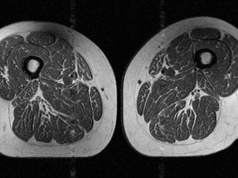

Ludzkie udo jak stek. Tak zmienia nas popularna żywność

Ludzkie udo jak stek. Tak zmienia nas popularna żywność

Najnowsze badania naukowców, opublikowane w czasopiśmie Radiology i prezentowane przez Radiological Society of North America (RSNA), pokazują niepokojące zjawisko. Dieta bogata w żywność wysoko przetworzoną powoduje okładanie się tłuszczu nie tylko p...